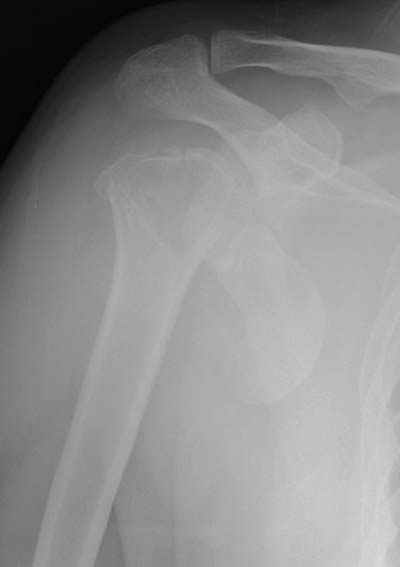

Здесь случай перелома-вывиха плеча, больному 56 лет, после "дважды" закрытой неудачной репозиции, опять же ургентно взяли в операционную, после полного общего обезболивания попытались сделать репозицию, и фиксацию провели спицами.

Больной находился в повязке, примерно напоминяющей косыночную, рекомендованы движения в локтевом суставе и маятниковые движения в плече, спицы удалены в три недели (были случаи миграции)

Больной амбулаторный, предупрежден на случай осложнения АВН головки.

Клинические снимки - 3 недели после операции